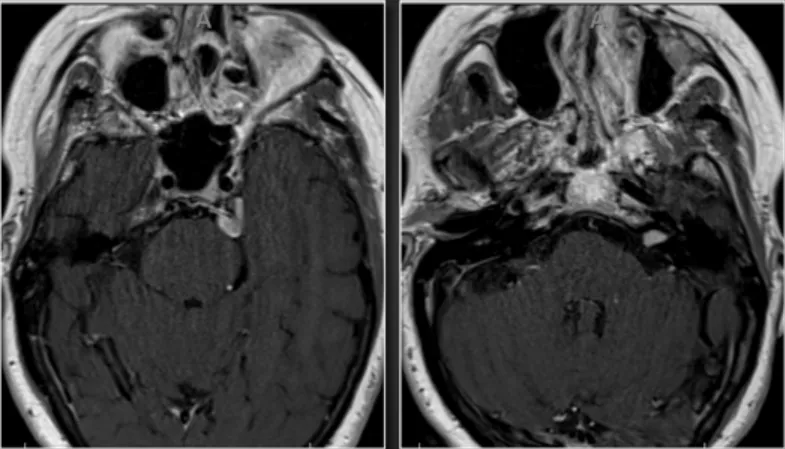

69岁女性,因顽固性左侧面部疼痛伴轻微左耳听力下降就诊。影像学检查提示左侧岩尖/梅克尔腔脑膜瘤(13.0×8.1毫米)及左侧内听道听神经瘤(8.8×5.6毫米)。两种肿瘤,一处是疼痛的元凶,一处是听力的威胁,都藏匿在颅底最复杂的区域。

(术前MRI)